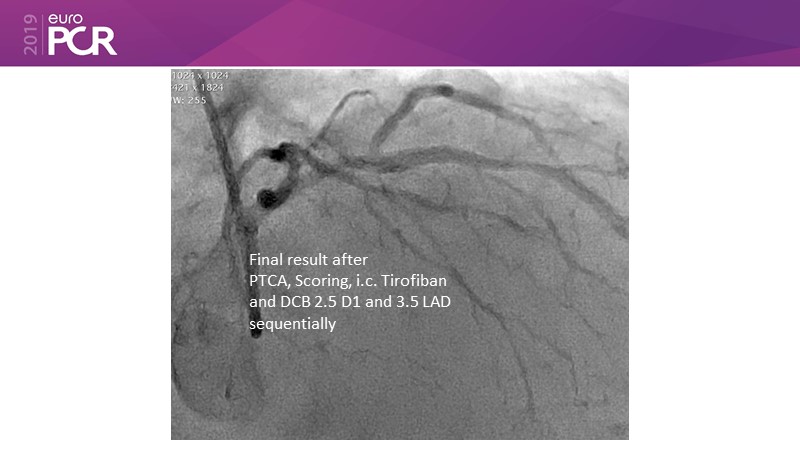

Go implant-free in de novo lesions: DCB-only strategy

Consult this session to learn about the DCB-only concept, treatment methodology and consensus group recommendations, and discover the latest scientific evidence of DCB-only in de novo lesions and in complex PCIs.